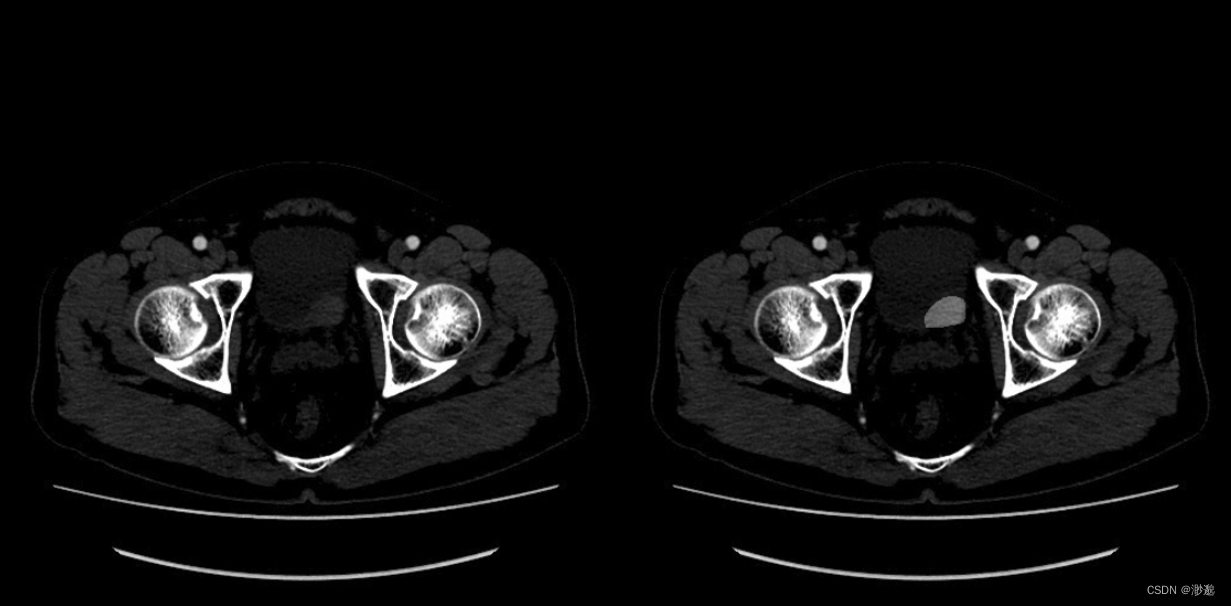

为了更好的查看mask在原始影像的位置,我们需要将mask覆盖到原始影像上。

#orijpgpath:原始影像的jpg图像所在文件夹

#alpha:勾画覆盖强度

执行完毕后将得到以下图像:左侧为原始影像,右侧为勾画覆盖影像。